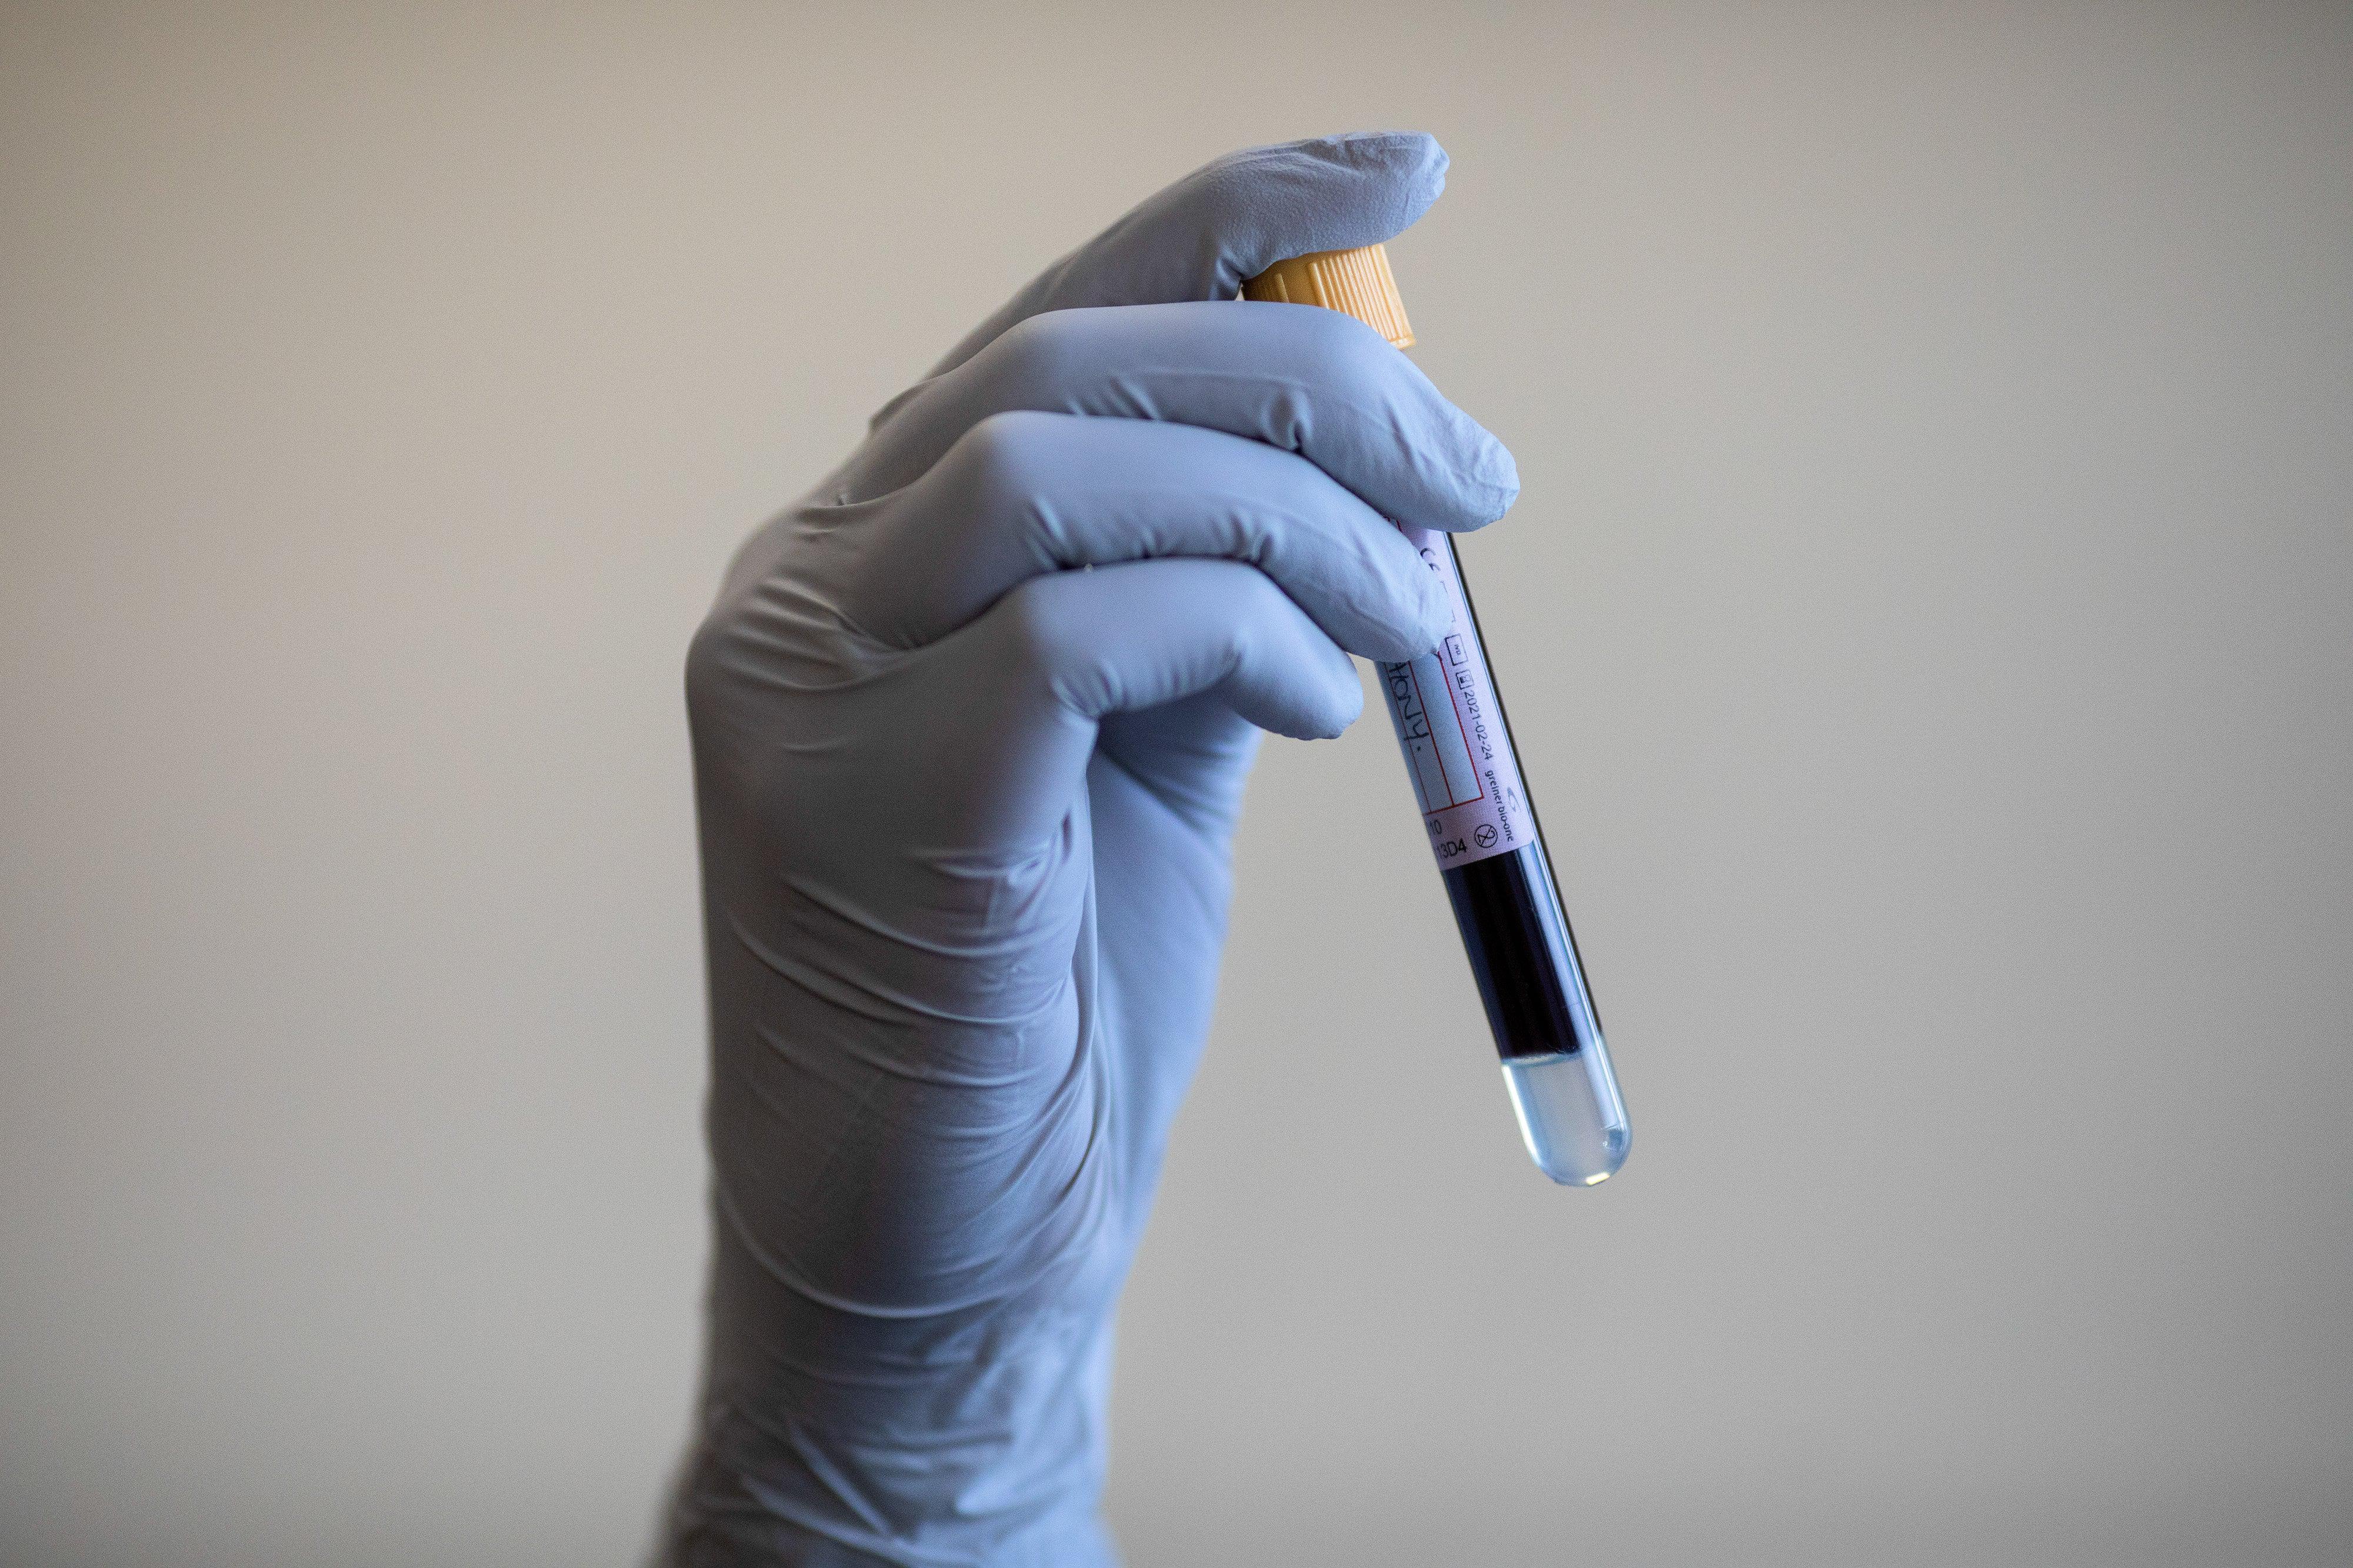

Alzheimer’s blood tests predict the average age at which the disease may strike, study finds

研究发现,阿尔茨海默病血液测试可以预测该病发作的平均年龄

Alzheimer’s blood tests predict the average age at which the disease may strike, study finds

研究发现,阿尔茨海默病血液测试可以预测该病发作的平均年龄

2026-02-19

894词 中等